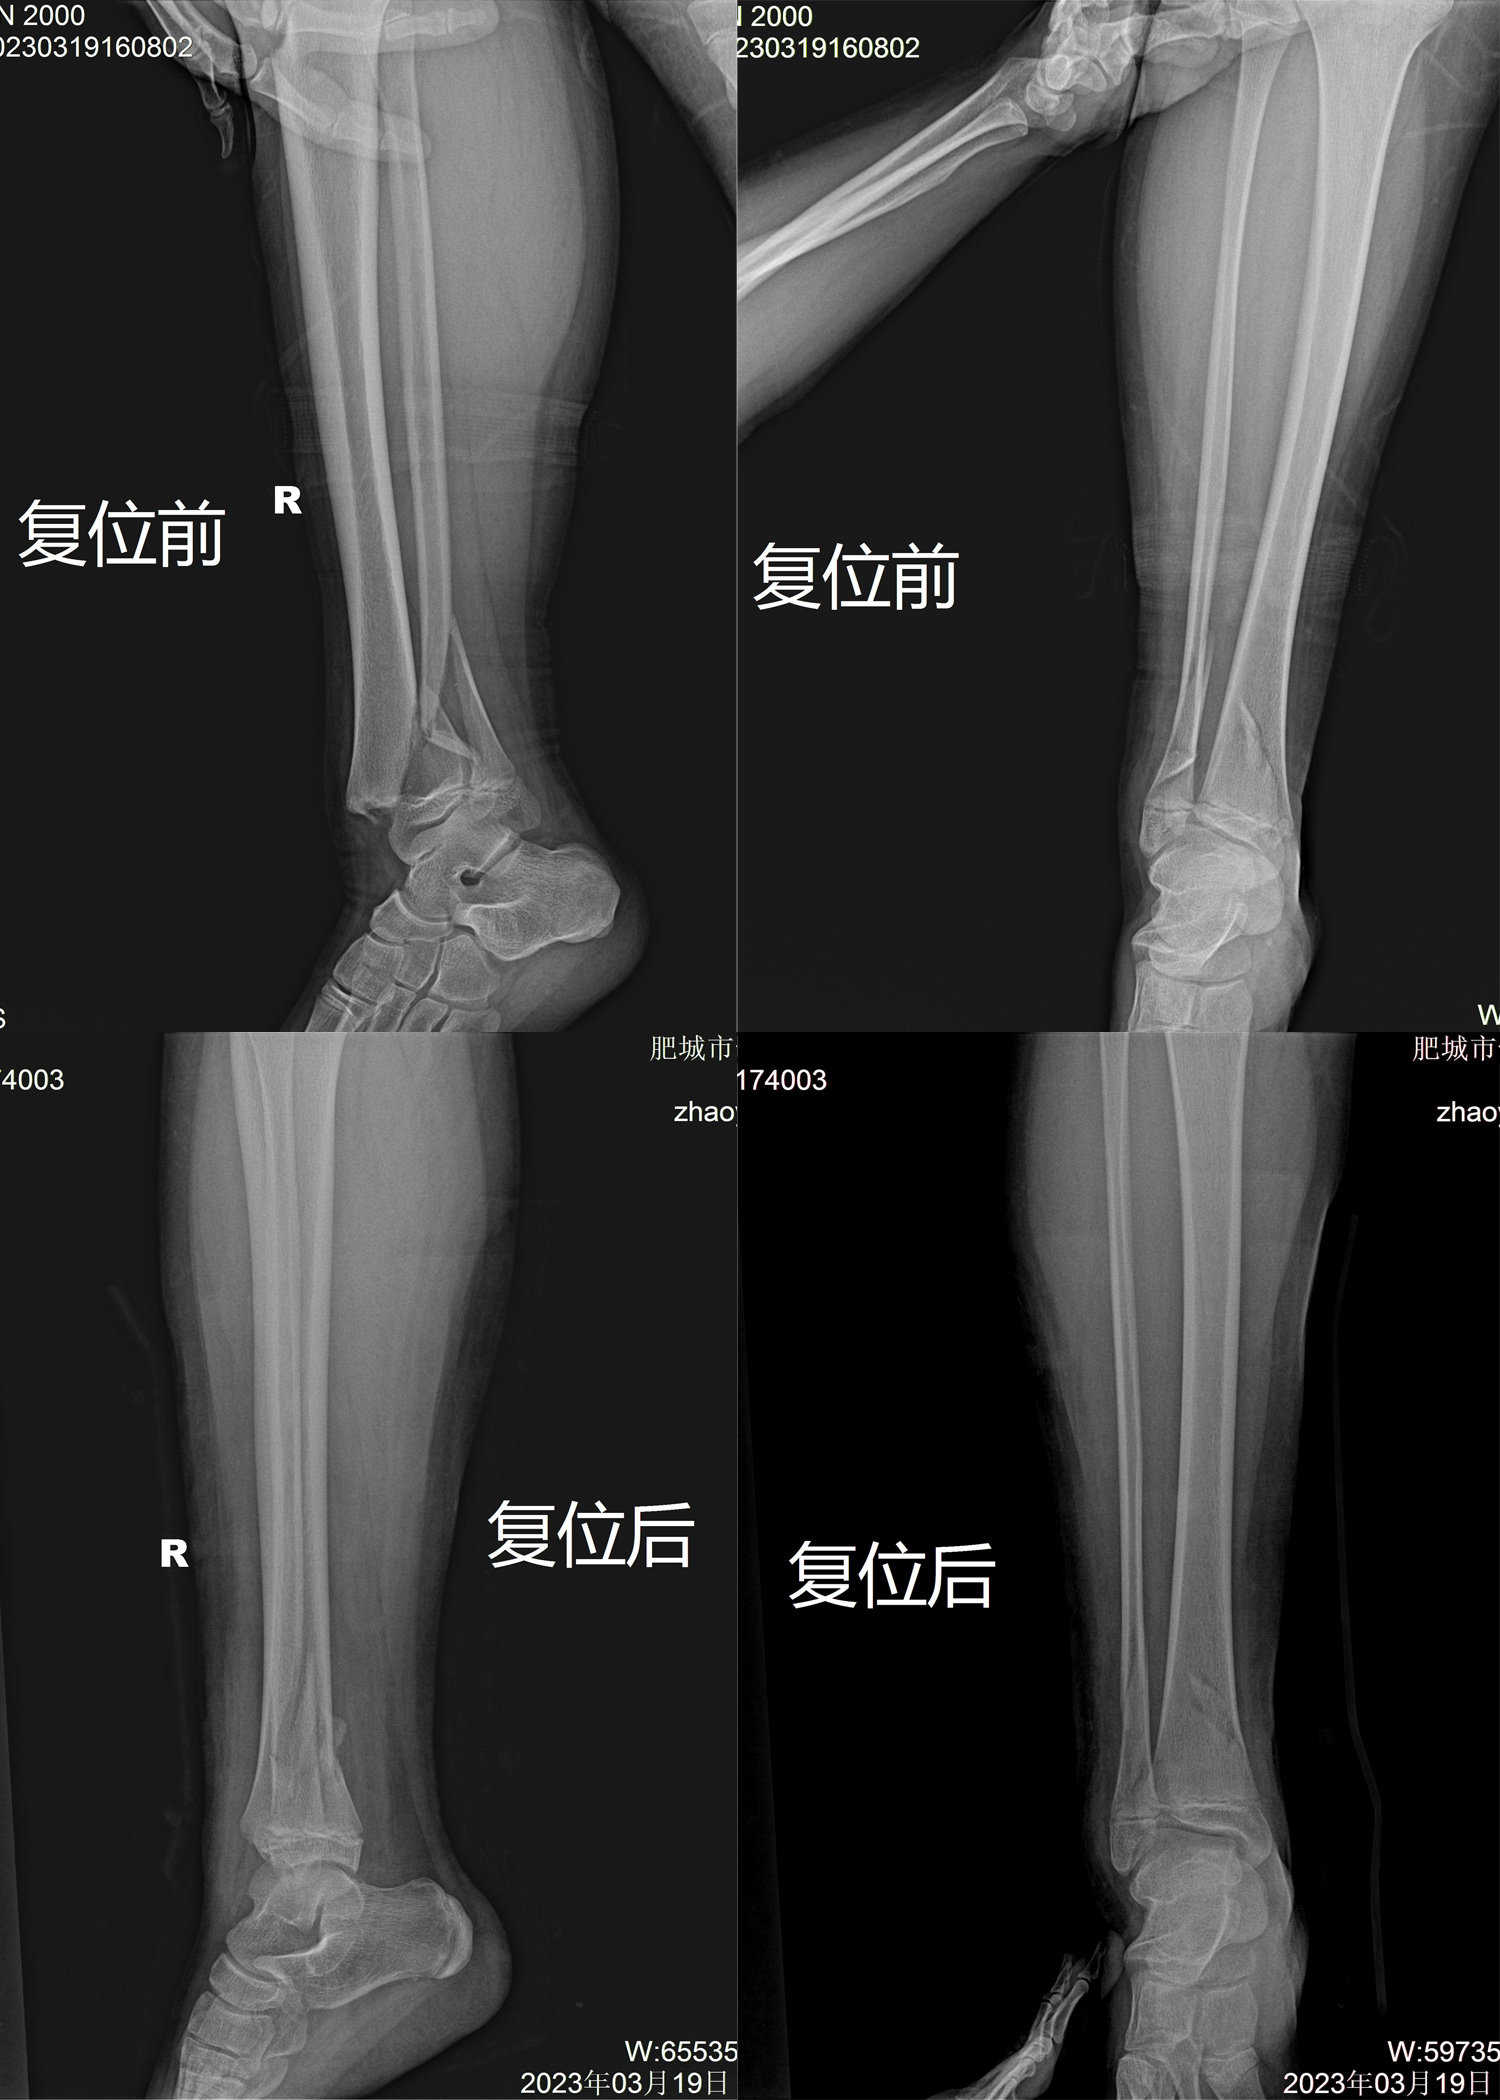

梁氏正骨-杨乐正骨案例